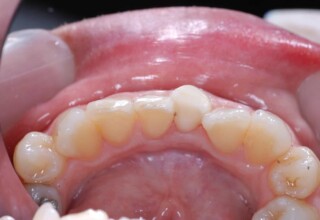

Οι όψεις πορσελάνης είναι ο καλύτερος τρόπος αντιμετώπισης αισθητικών προβλημάτων στην πρόσθια περιοχή του στόματος. Συνδυάζουν συντηρητική αφαίρεση οδοντικής ουσίας και πολύ υψηλή αισθητική απόδοση. Στο παρακάτω εκτεταμένο περιστατικό υπήρχαν: παλαιά σφραγίσματα, δυσχρωμίες, κακό σχήμα και μήκος δοντιών, κακή αναλογία δοντιών-ούλων. Έγινε προσεκτικός εργαστηριακός σχεδιασμός σε εκμαγεία απ’όπου προέκυψαν προσωρινές όψεις που τοποθετήθηκαν στο στόμα για δοκιμή και διορθώσεις. Όταν οριστικοποιήθηκαν οι μετατροπές, οι προσωρινές χρησιμοποιήθηκαν σαν οδηγός για τις μόνιμες. Οι πέντε μόνιμες όψεις πορσελάνης που κατασκευάστηκαν για τα πέντε πρόσθια δόντια της άνω απεκατέστησαν σχεδόν άψογα την αισθητική εμφάνιση της ασθενούς.